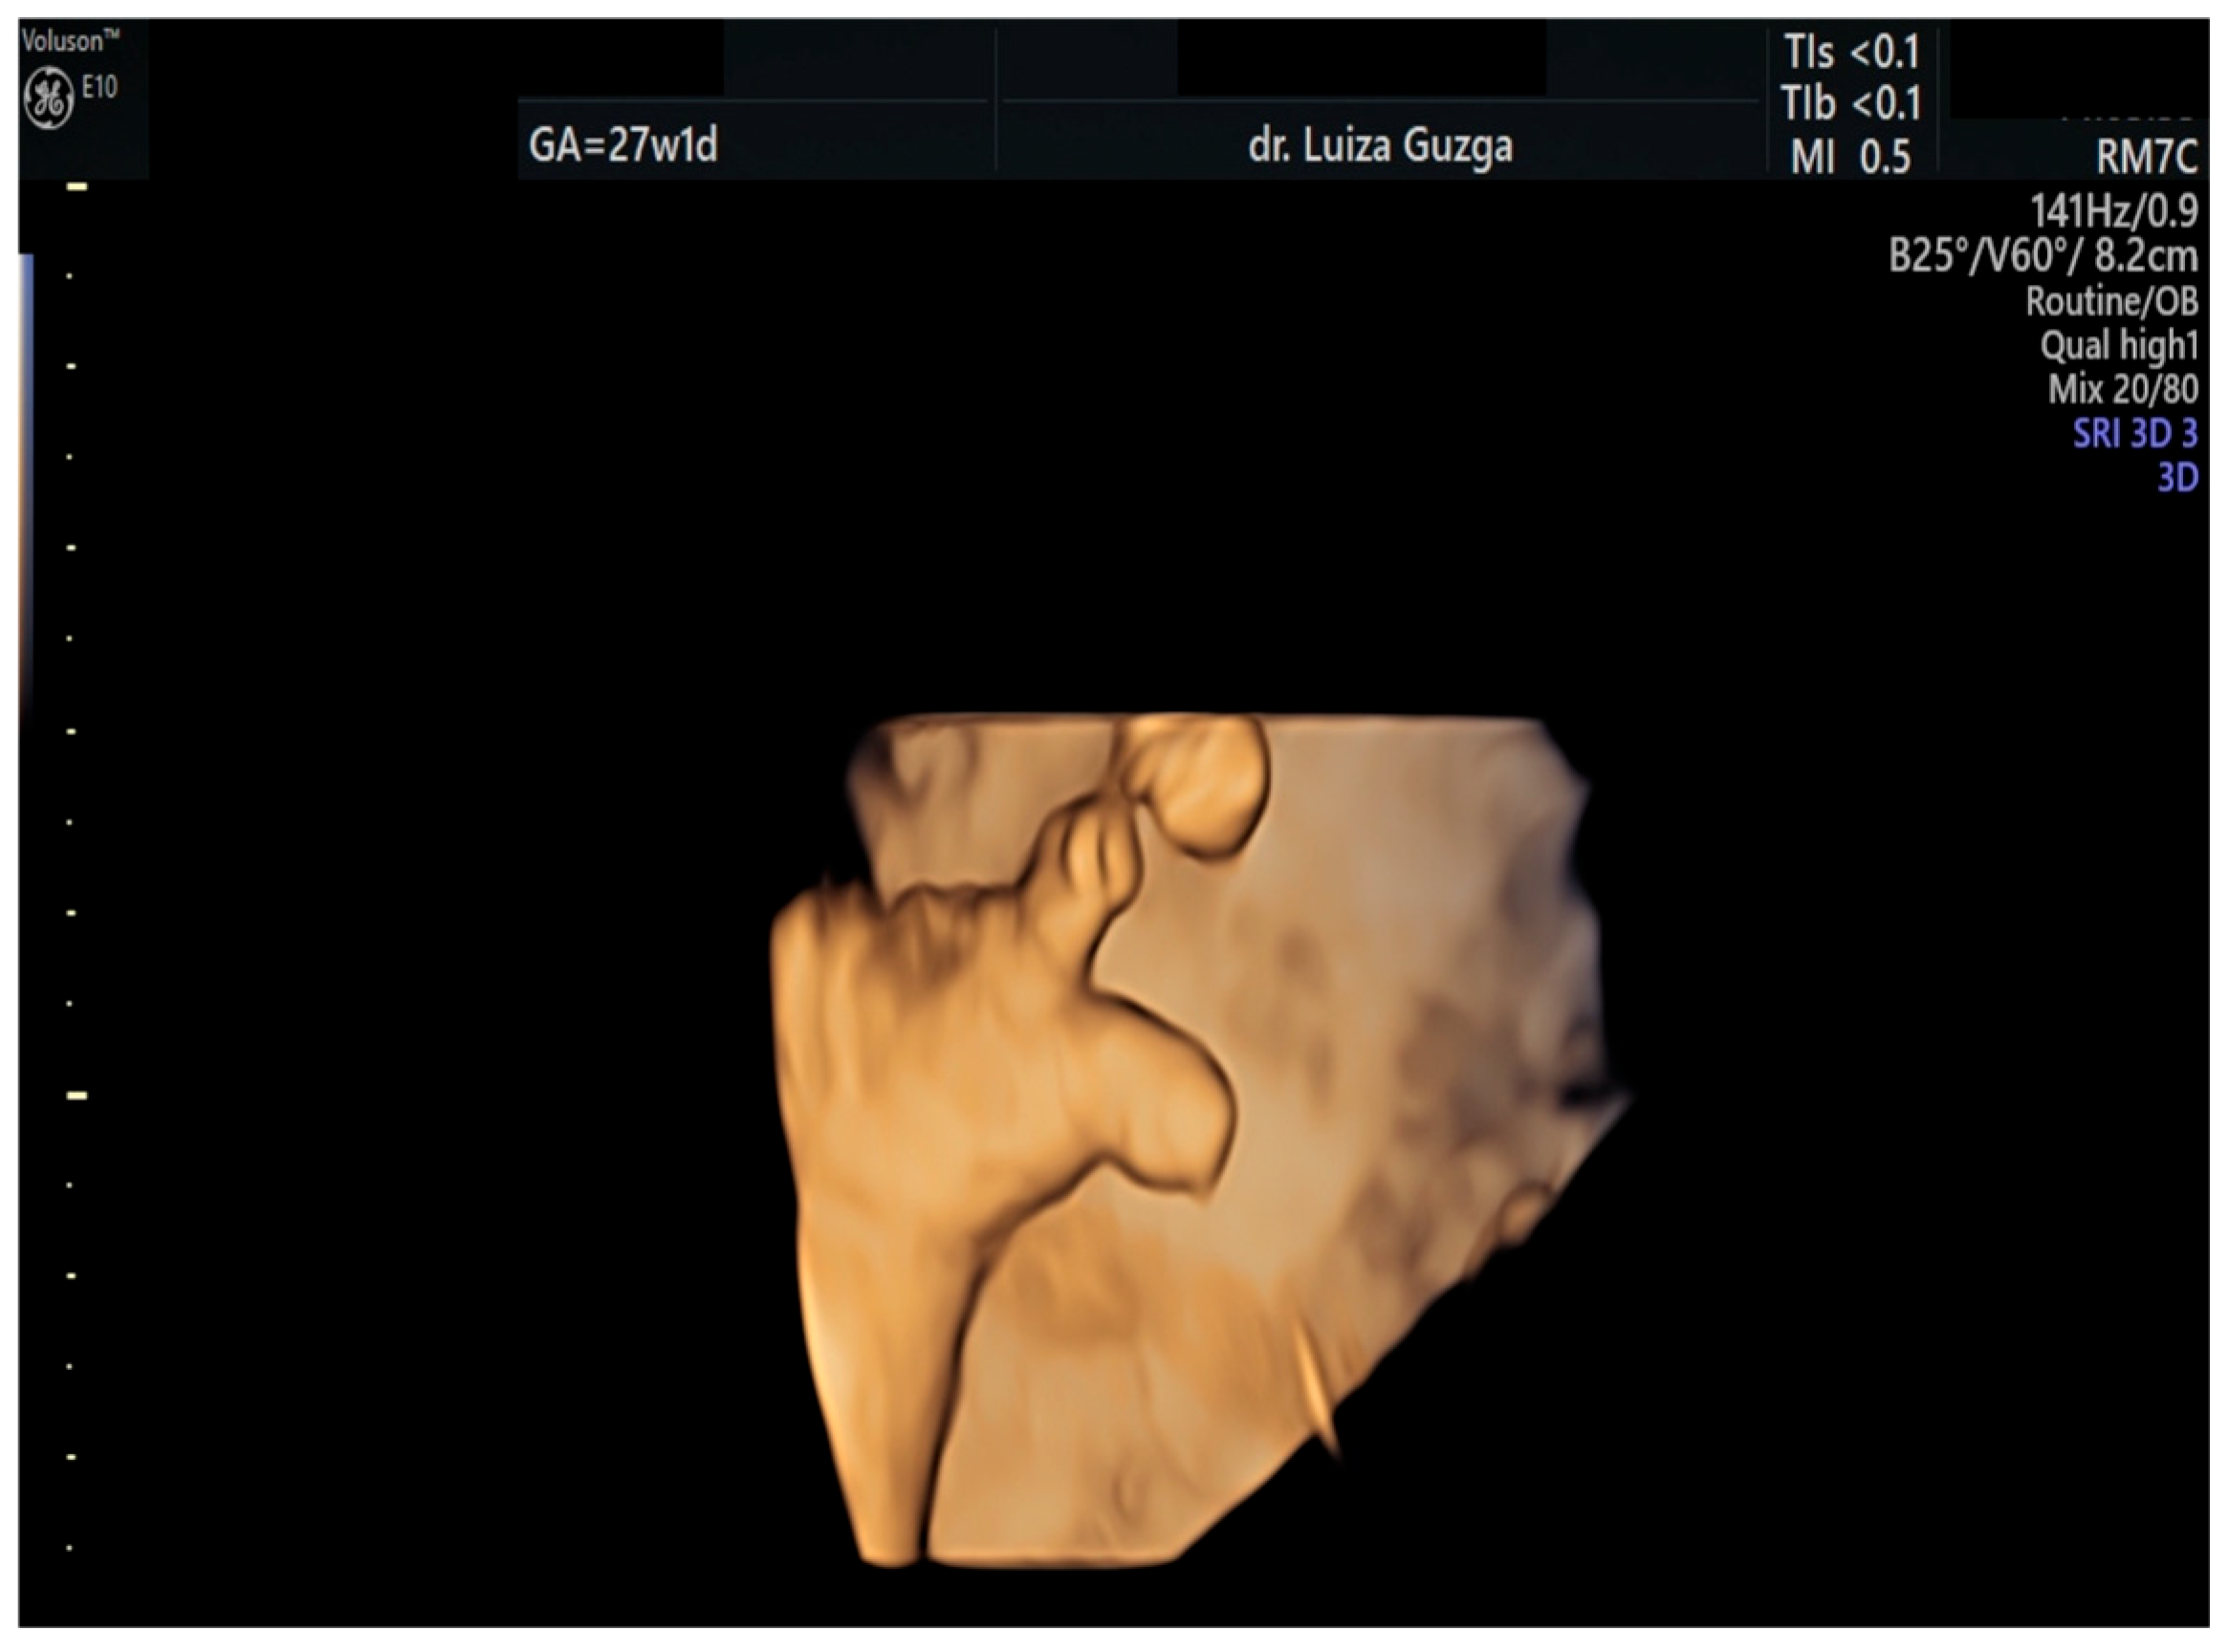

2.1. Case Presentation

2.2. Case Management

| Pointed forehead/premature closure of the metopic suture | - | + | +++ | ? |

| Hypotelorism | - | + | +++ | Rather hypertelorism |

| Micrognathia/small chin size | - | + | +++ | +++ |